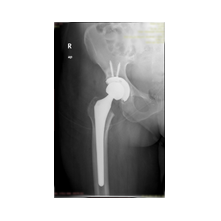

Peki kalça protezi ameliyatın da neler yapıyoruz? Diz protezi ameliyatındaki benzer aşamaları uyguluyoruz. Kalça eklemi dize göre yapısal olarak ve çalışma sistemi olarak farklıdır. Kalça eklemi bir yuva ve onun içinde hareket eden femur başı dediğimiz bir toptan oluşur. Kalça eklemi kireçlenmesinde bu baş ve yuva yüzeyindeki kıkırdakların aşınması sonucu başın yuvarlaklığı kaybolur, sonuçta ağrı ve hareket kısıtlılığı ortaya çıkar. Bu yüzeyleri değiştirirken öncelikle bu başı kesip atıyoruz. Daha sonra yuvayı yine kılavuzlarla oyup uygun büyüklükteki protezi sıkıştırdıktan sonra en az 2 vida ile kemiğe adapte ediyoruz. Daha sonra alt uyluk kemiğini yine kılavuzlar yardımı ile oyduktan sonra kemiğe adapte ediyoruz ve sistemi birleştiriyoruz.

Görüntüleri büyütmek için üzerine tıklayınız.